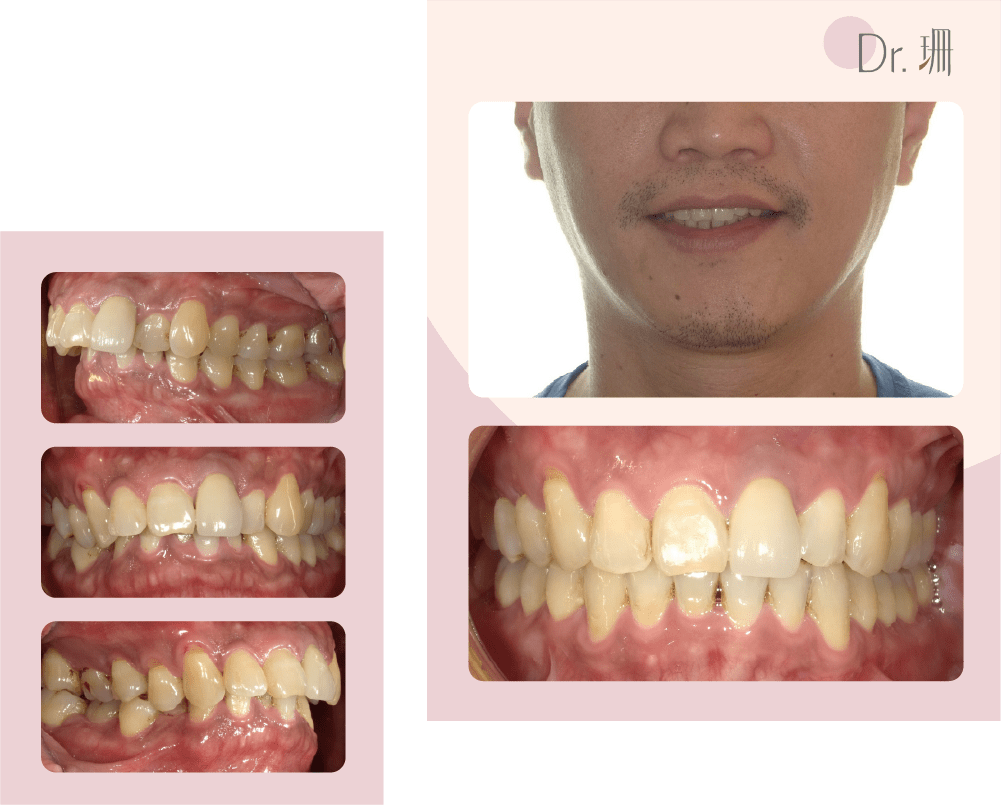

牙齒擁擠、深咬、上下門牙水平距離大

牙齒矯正前後外觀及牙齒變化

阿琪療程結束時真的很讓我驚艷感動! 因為輪廓明顯改善,看上去年輕許多,衣服也越穿越帥,整個氣息都不一樣了呢!